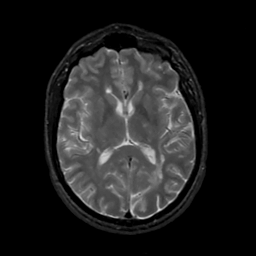

MR Study #3, February 24, 1991 -- Slice #27

[Home][Help][Clinical][Tour 1][Tour 2] Slice 27